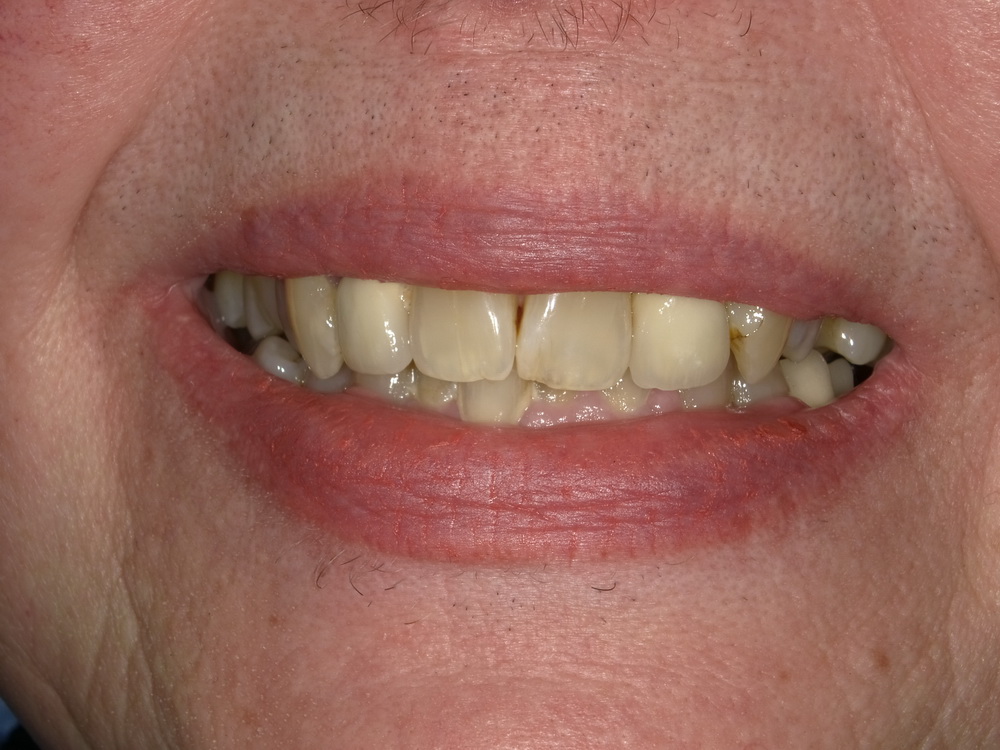

CMD-Patientin ausdem Schaumburger Land beginnt mir der Funktionstherapie

Nun soll es losgehen, was in den vergangenen Monaten systematisch vorbereitet wurde.

Es beginnt mit der Versorgung der Oberkieferseitenzähne mit Laborgefertigten Dauerprovisorien.

Das war der Zustand im September 2025.